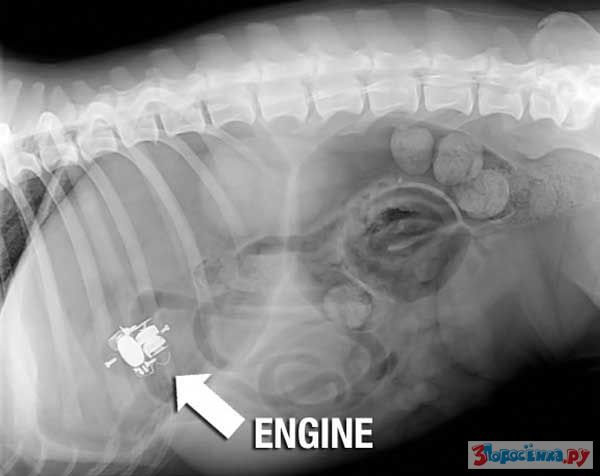

Нет ничего не перевариваемого

Некоторые собаки видимо полагают что их желудок способен переварить все на свете.